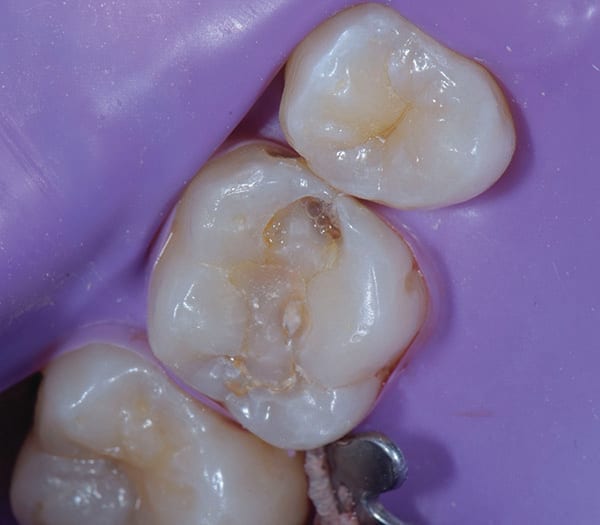

Once the operative field was isolated, a No. 557 carbide bur was used in a high-speed handpiece to efficiently remove the existing composite restoration and extend the preparation mesially. The Class II preparation was then refined using a fine diamond chamfer bur. Initial caries removal was performed using a round carbide bur in a slow-speed attachment (Figure 2). After initial caries removal, a caries indicating solution (Seek™ Caries Indicator, Ultradent) was used to stain any suspected remaining caries (Figure 3).4 Caries indicating solutions target demineralized dentin with a highly visible stain, providing an efficient and effective means of ensuring that only the infected dentin is subsequently removed, leaving the affected dentin behind (Figure 4).